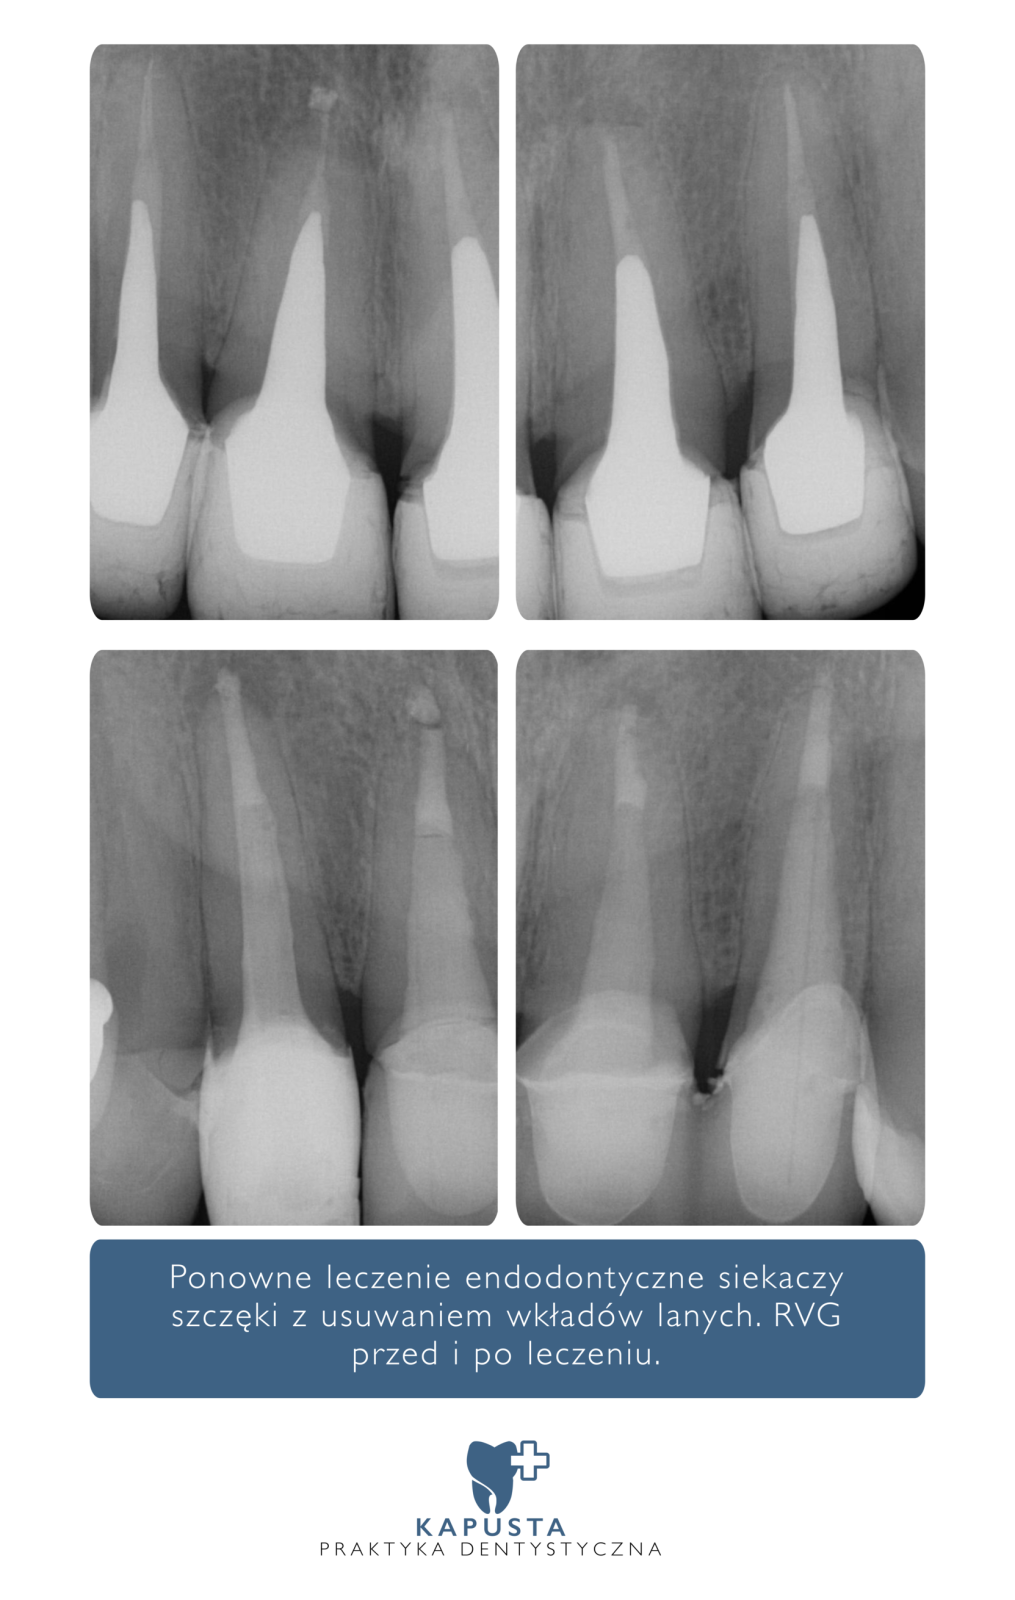

Leczenie endodontyczne – realizacje